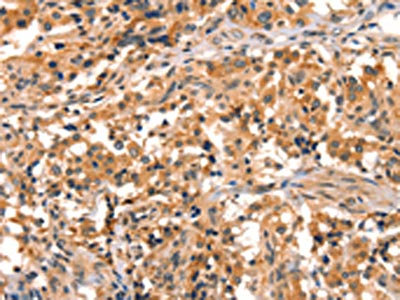

• The image on the left is immunohistochemistry of paraffin-embedded Human liver cancer tissue using CSB-PA584449(EPPIN Antibody) at dilution 1/25, on the right is treated with synthetic peptide. (Original magnification: ×200)

• The image on the left is immunohistochemistry of paraffin-embedded Human thyroid cancer tissue using CSB-PA584449(EPPIN Antibody) at dilution 1/25, on the right is treated with synthetic peptide. (Original magnification: ×200)